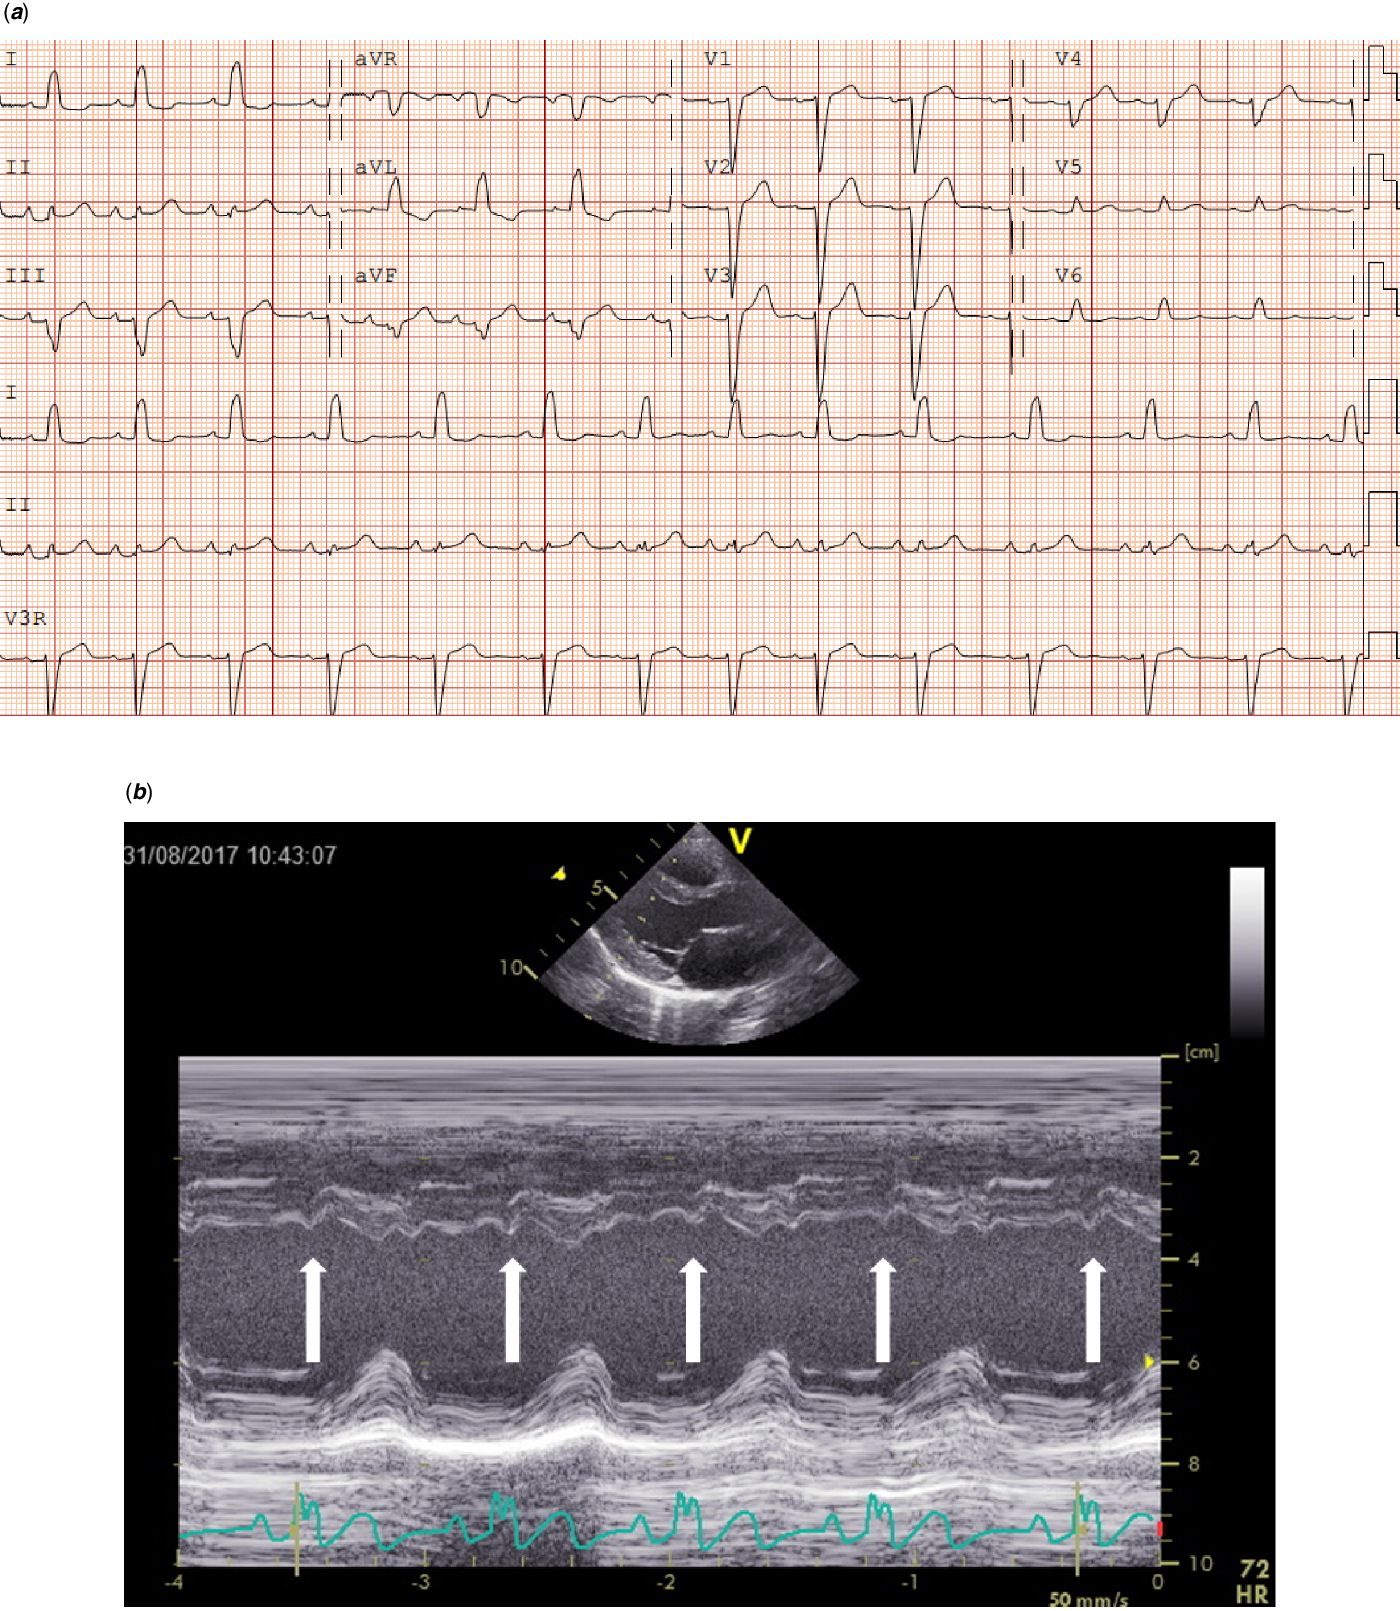

Regarding the 36 patients without a CHD, 15 (41.7%) had specific Noonan syndrome-related electrocardiographic features. These electrocardiographic features were seen in patients with mutations in PTPN11, SOS1, KRAS, CBL, BRAF, and A2ML1 genes (Table 3). Left axis deviation was seen in 12 (33.3%) patients, small left precordial R-waves in 7 (19.4%) patients, large right precordial S-waves leads in 2 (5.6%) patients, and wide QRS complex in 1 (2.8%) patient (Table 3). One child with a SOS1 mutation without CHD had a complete left bundle branch block with left axis deviation with a septal flash on echocardiography (Fig 2a and b).

Figure 2. ( a ) Electrocardiogram (speed 25 mm/sec, voltage 0.1 mV/mm) from an 8-year-old girl with a SOS1 mutation with complete left bundle branch block (LBBB). In addition to an duration increase in QRS, please note the distinctive mid-QRS notching in leads I and aVL, along with mid-QRS-slurring in leads V5 and V6. ( b ) Echocardiographic assessment of the septal movement in the long-axis in this patient revealed a septal flash (white arrows), which is a marker of left ventricular electromechanical desynchrony in the presence 'of LBBB.